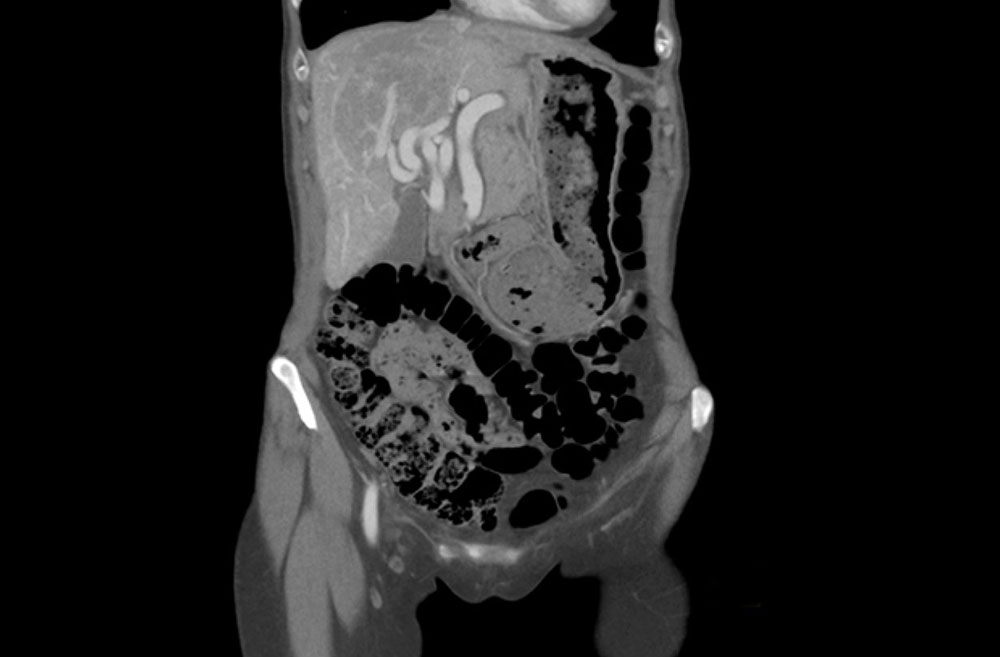

For hepatic vascular malformations (arteriovenous, arterioportal, and portovenous shunts), postprandial capsular pain is the typical symptom.